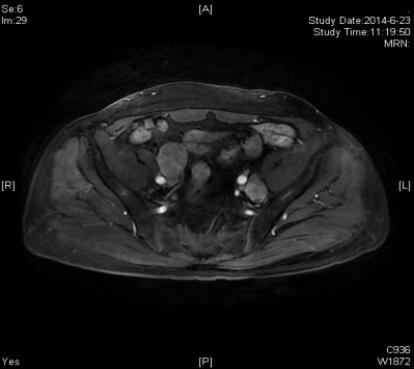

患者此时的ECT骨扫描典型图片如下:

程竟仪教授:我来解读一下此患者的ECT骨扫描。患者全身ECT骨显像显示T11椎体放射性摄取增高,其余骨骼未见放射性异常分布。对于骨骼的单发“热区”,尤其是脊柱的单发病灶,诊断比较困难,原因在于脊柱单发病灶诊断的假阳性率高,尤其在老年,退行性改变、压缩性骨折都会出现类似的表现。因此,在平面扫描的基础上,加做SPECT/CT局部断层显像,引入CT的解剖信息,与核医学的功能影像信息进行同机融合分析。断层显像可见T11左半椎体骨质致密、密度不均,累计椎板和椎弓根,相应部位放射性摄取异常增高,再结合患者治疗前基线评价、生化复发的病史,诊断为T11椎体转移。后患者进行MRI显像,与前述诊断一致,相互印证。